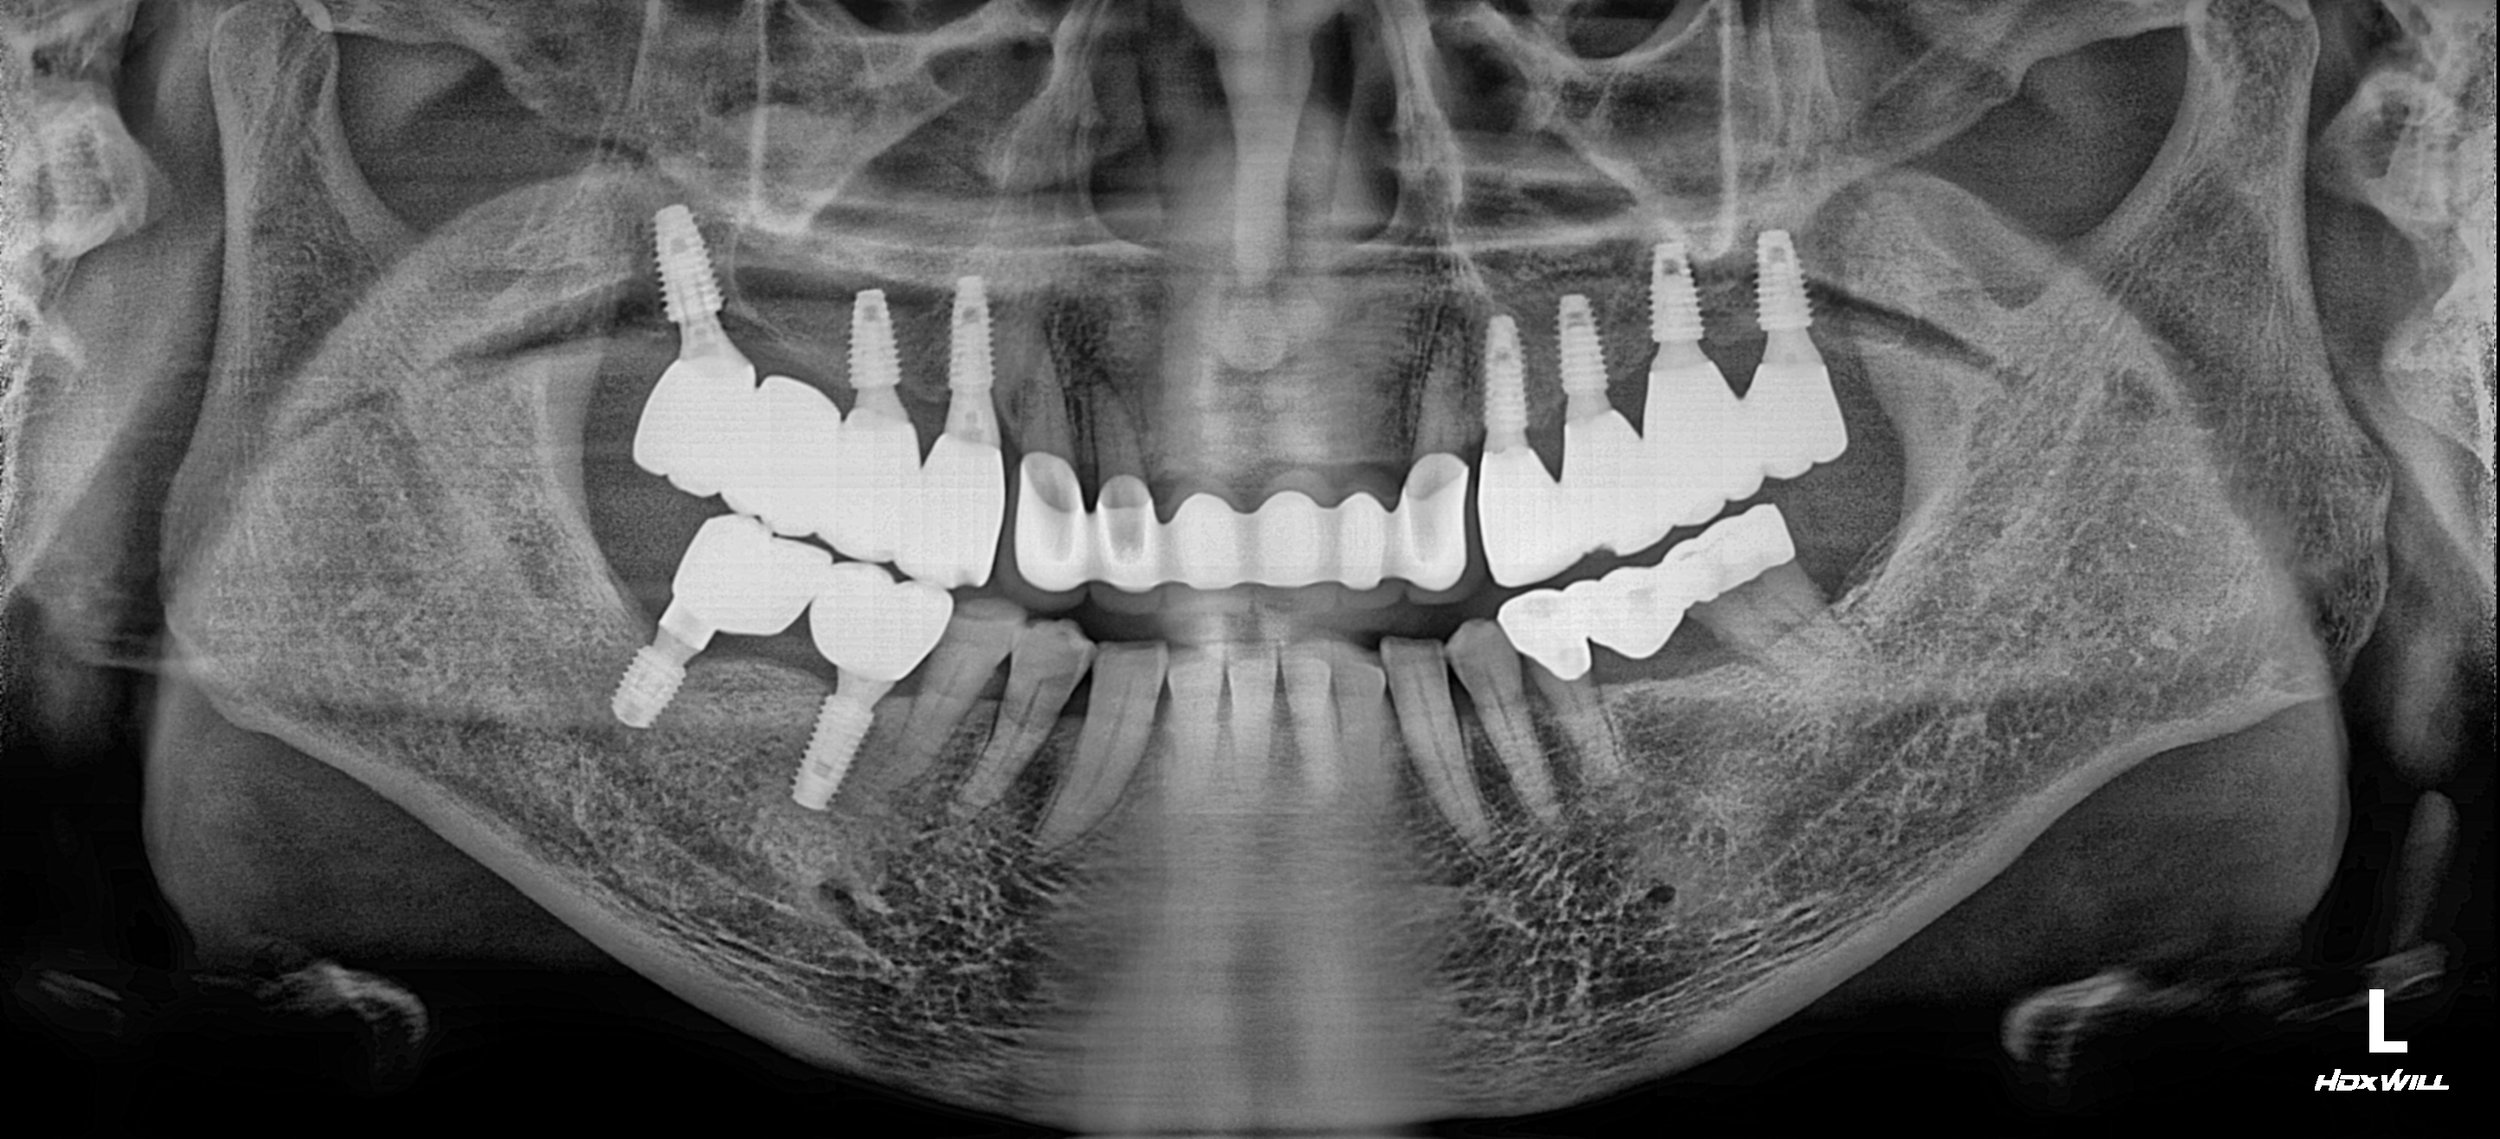

INTRA ORAL - BEFORE

The primary clinical findings included:

• Posterior Bite Collapse: Loss of posterior support resulting in a reduced Vertical Dimension of Occlusion (VDO).

• Pathological Anterior Flaring: Without posterior stops, excessive forces caused the maxillary anterior teeth to drift labially (flaring), creating aesthetic and functional distress.

• Failing Prosthetics & Periodontitis: Existing restorations were ill-fitting, and generalized periodontal disease had further destabilized the remaining teeth.